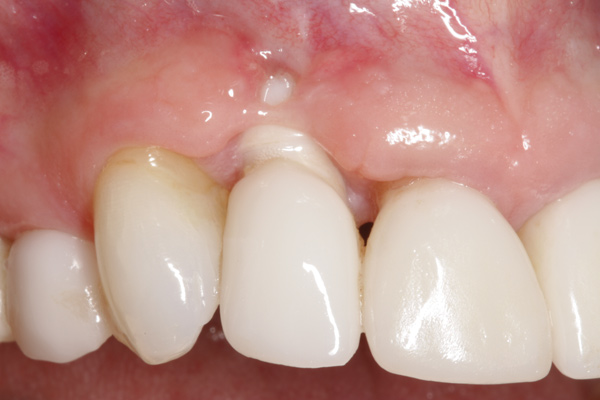

To predict peri-implant esthetic outcomes, Kois described five essential diagnostic keys that need to be assessed before removing a periodontally hopeless tooth (Figure 3 and Figure 4): (1) relative tooth position; (2) form of the periodontium; (3) periodontal biotype; (4) tooth shape; and (5) position of the osseous crest. Failing teeth that have a thick, flat gingival biotype, are square shaped, and have < 3 mm vertical distance from the position of the facial and interproximal crest have the lowest risk of developing recessions after implant placement.23 Therefore, implant surgery may be performed by either an open flap or flapless approach. However, teeth with a thin soft-tissue biotype, a highly scalloped gingival architecture, and a triangular shape that are positioned facially have less-predictable peri-implant esthetic outcomes. When a tooth presents with these unfavorable anatomical features, grafting procedures should be considered both before and after tooth extraction to prevent vertical loss and facial collapse of the gingival architecture.21 Flapless tooth extraction should be attempted in the esthetic zone to maintain blood supply from the periosteum and endosteum and maximize healing potential (Figure 5).44 In addition, several surgical protocols have been proposed to avoid peri-implant mucosal recessions, including 3-dimensional implant positioning,45,46 the use of platform-switching implants,47,48 and soft-tissue augmentation.8,49,50